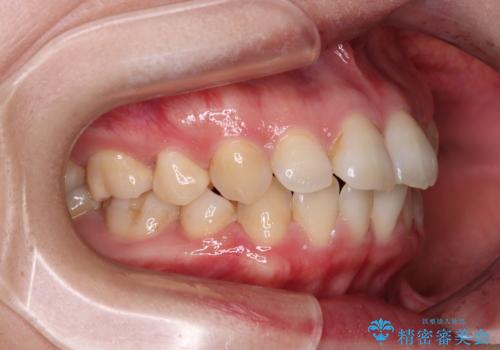

- 上下前歯の後戻りを気にして来院された患者様です。

インビザラインでの治療を希望されていて、デコボコの程度が中等度であり、安価なパッケージにて対応可能と判断されたため、インビザライン・モデレートを用いて矯正治療を行うこととしました。